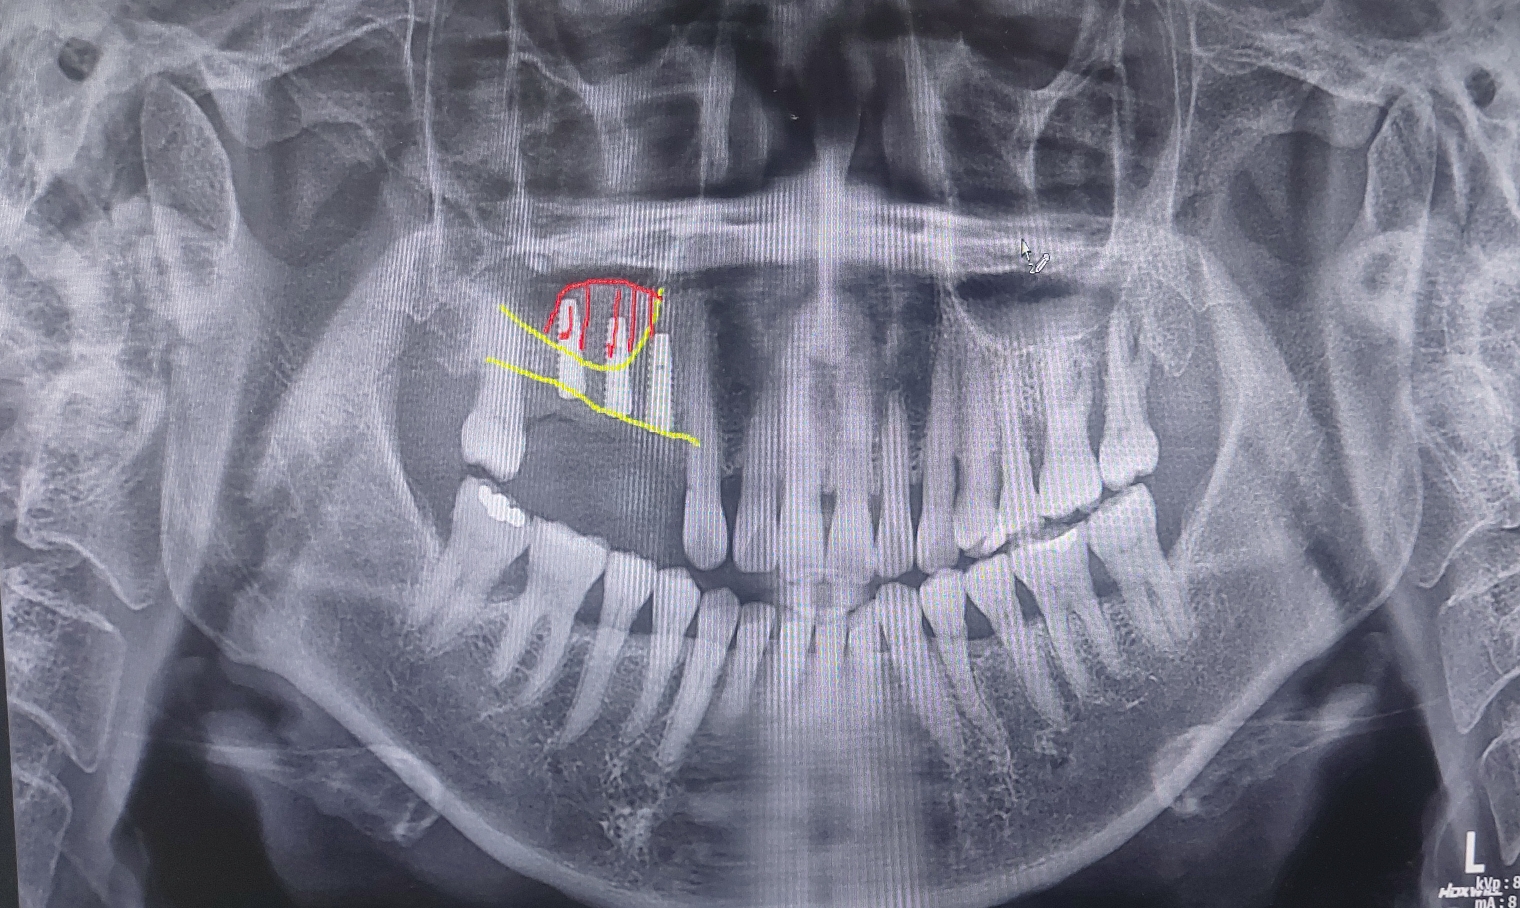

이번 포스팅에서는 사진을 보면 막연하던 상악동거상술이 어떻게 진행되었는지를 알 수 있습니다.

그냥 코옆 공기 주머니에다가 이식한다고 하면 환자분이 막연하게 생각하실수 있겠지만

위의 사진을 본다면 구체적으로 어떤 방법으로 진행되는지 감을 잡을 수 있을 겁니다.